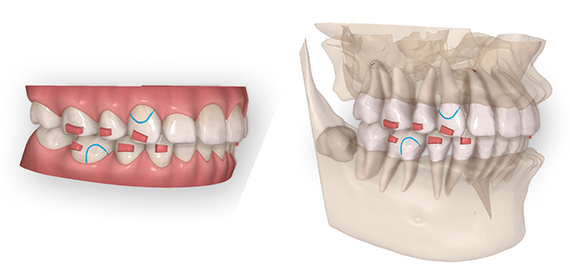

マウスピース矯正では、治療開始前の精密検査のデータをもとに、3Dの治療計画ソフトウェアを使って、治療開始から治療終了までの歯の動きを3Dシミュレーションで見ることができます。

この3Dシミュレーションは、CT撮影で得られた骨のデータと重ね合わせすることができ、より安全に歯の移動を診断し、治療計画を立てることができます。

患者様の歯並びを綺麗にして口元を自然な美しさに改善するために、歯を見るだけではなく、お顔と歯並びのバランスを考え、デジタルを駆使して総合的に診断致します。

正面だけでなく、横顔の診断も大切にしています。お口元が出でいる方は、前歯を後ろに移動させると、とても綺麗な口元の印象に変わります。

そこに歯科医師の診断の差が出ます。口元が綺麗になると人生が変わります!